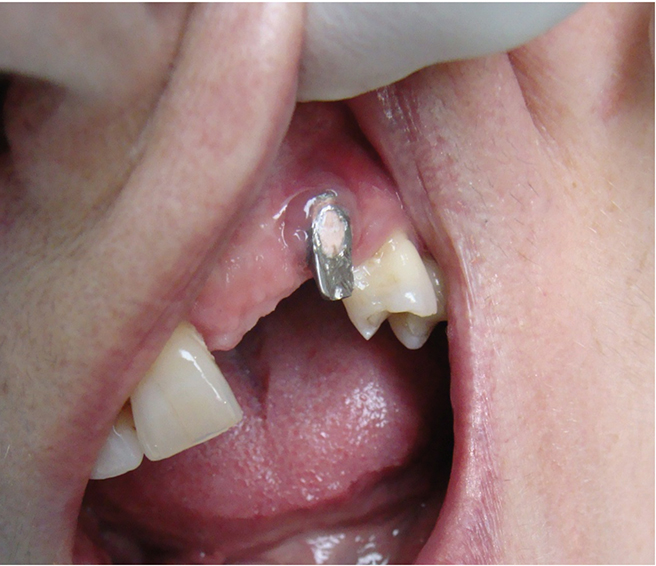

Above: A case of peri-implantitis requiring debridement and bone grafting.